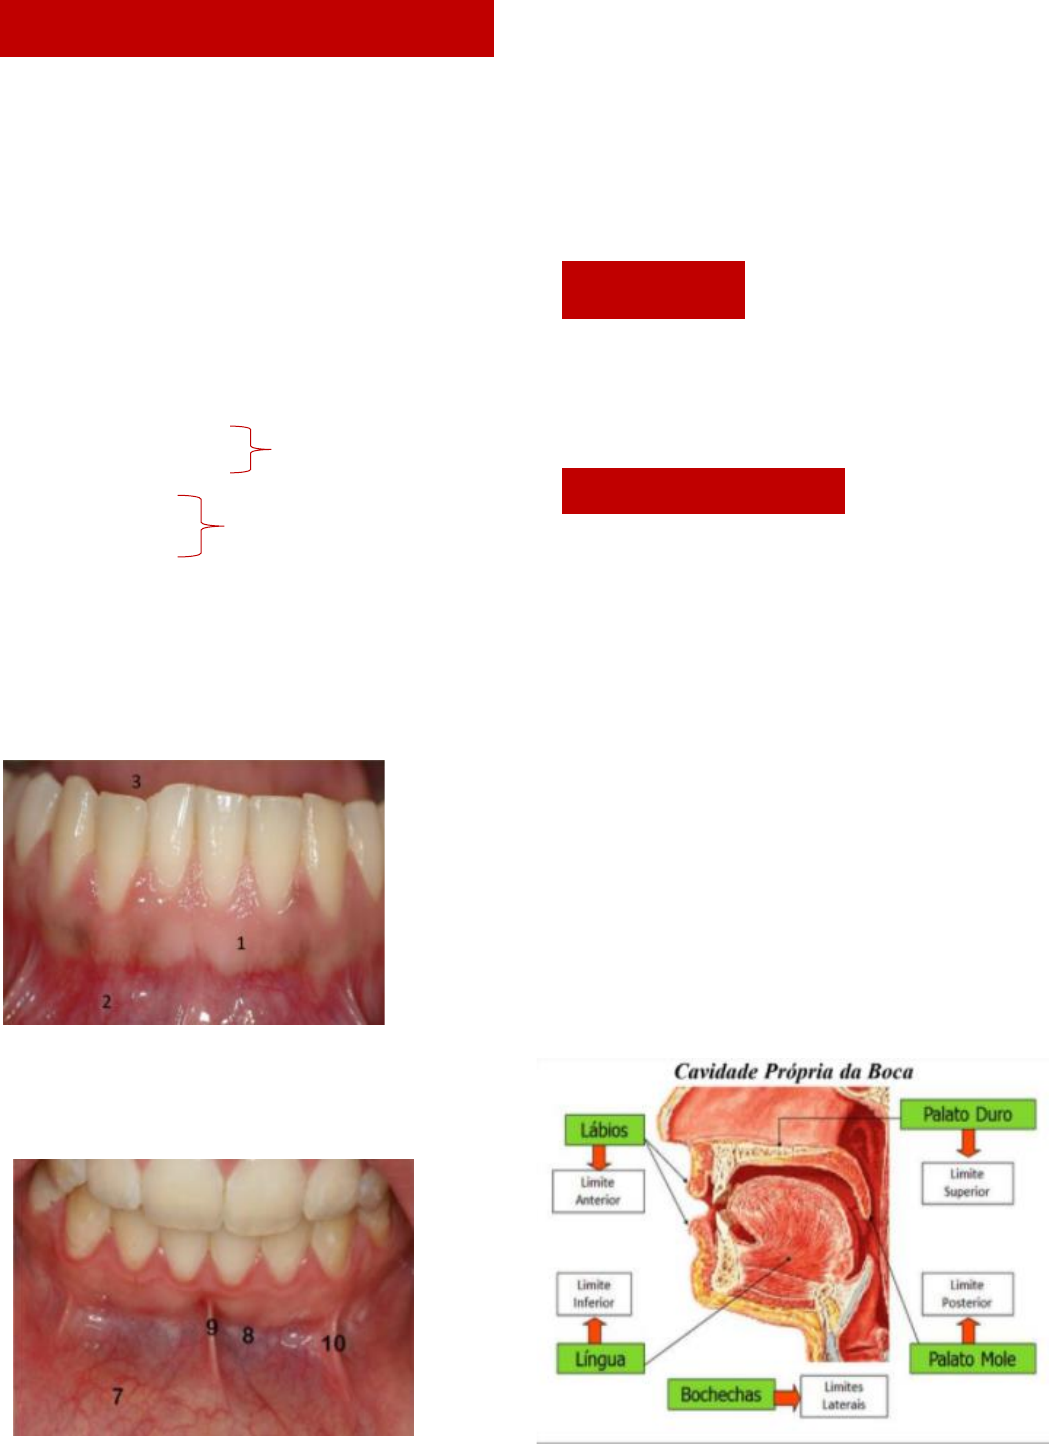

1. Mucosa alveolar

2. Vestíbulo da boca

3. Cavidade própria da boca

Vestíbulo da boca

7. Mucosa labial

8. Fórnice de vestíbulo

9. Freio labial inferior

10. Freio lateral

Vestíbulo da Boca: é o espaço semelhante a uma

fenda entre os dentes e a gengiva e os lábios e as

bochechas – espaço virtual, só visualizados de os

lábios forem puxados

Cavidade Própria da Boca: é o espaço entre os

arcos dentais superior e inferior, onde fica a língua

Boca

Delimitada por 6 paredes:

Parede anterior (1) – lábio

Paredes laterais (2) – bochechas

Parede superior (1) – palato duro

Paredes posterior (1) – palato mole

Paredes inferior (1) – soalho de boca

7 – Mucosa labial

8 – Fórnice de vestíbulo

9 – Freio labial inferior

10 – Freio lateral inferior